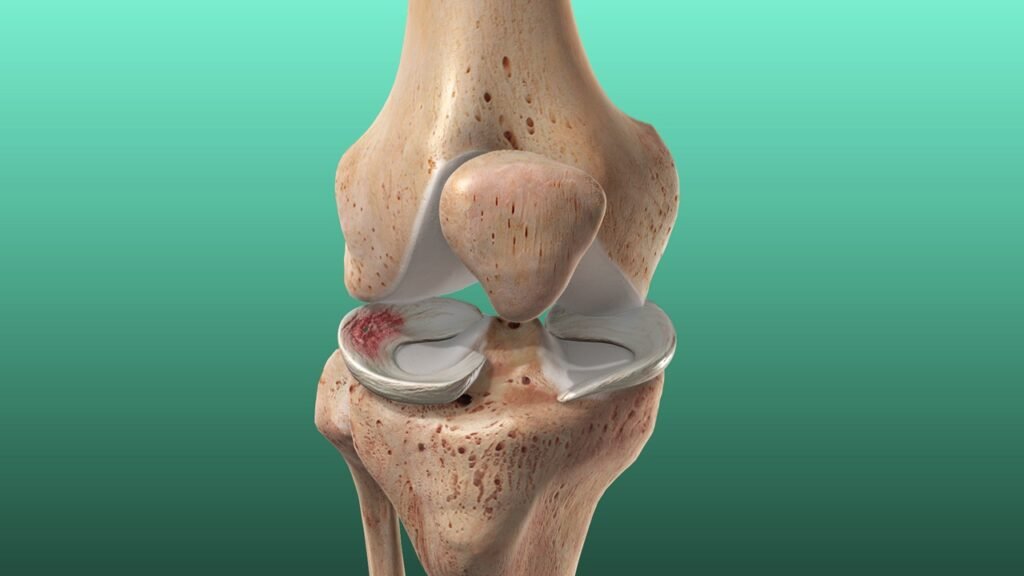

The meniscus is a C-shaped cartilage structure located between the thighbone (femur) and shinbone (tibia) in each knee. You have two menisci in each knee: the medial (inner) and lateral (outer). These structures play a vital role in absorbing shock, distributing weight, stabilising the joint, and protecting the smooth cartilage surfaces.

Whether a meniscus tear can be repaired depends on its type, location, and severity:

- Occur in the outer third of the meniscus (the red zone), where blood supply is better

- Occur in the inner two-thirds (the white zone), which lacks adequate blood flow for healing